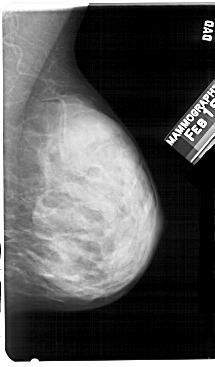

A_1326_1.LEFT_CC

LEFT_CC LINES 5356 PIXELS_PER_LINE 2986 BITS_PER_PIXEL 12 RESOLUTION 43.5 OVERLAY